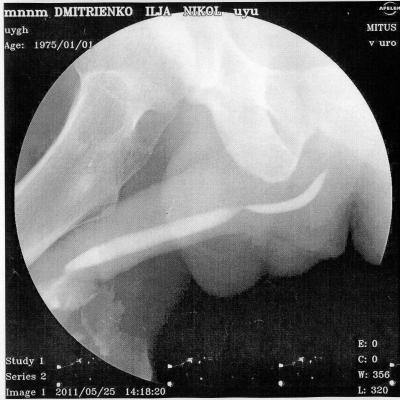

В начале 2011 года, в январе попал в , г. Алматы (был в командировке в Кзахстане)чеиспусканием, после проведенной уретроскопии, началось обострение, продержали в больнице неделю, вводили в/в антибиотики, была проведена инфузионно-детоксикационная терапия, физиолечение, делали восходящую и нисходящую уретроцистографии - б/о.

По приезду на Украину, боли не проходили в задней части уретры, было учащенное мочеиспускание, сдавал у местных урологов рахзличные анализы ПЦР на ЗППП - отрицательно, ОАМ, ОАК, различные посевы - все в пределах нормы. В конце марта сделал уже в г. Киева - КТ - на ней показало сужение простатической части уретры, было предложено бужирование, я отказался и поехал в Ростов, к профессору Когану, там провели исследования и сказали, что пока ничего не видят. Боли остаются, после полового акта боль усиливается, и учащается мочеиспускание. Не знаю, может быть болит семенной бугорок, могли задеть при уретроскопии, после которой и начались такие проблемы.